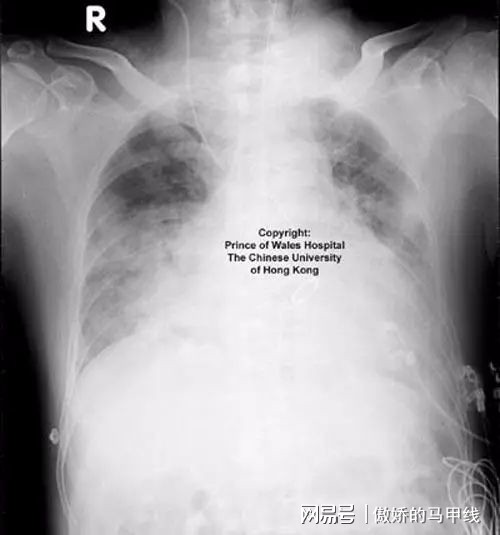

故事始于一个寒冷的冬日早晨,那天,小明突然感到身体不适,咳嗽得厉害,一开始,他并未在意,以为是普通的感冒,病情逐渐恶化,他的妈妈赶紧带他去医院,经过一系列检查,医生诊断他患上了肺炎,这个消息让全家都陷入了担忧,但妈妈与小明的朋友们并未放弃。